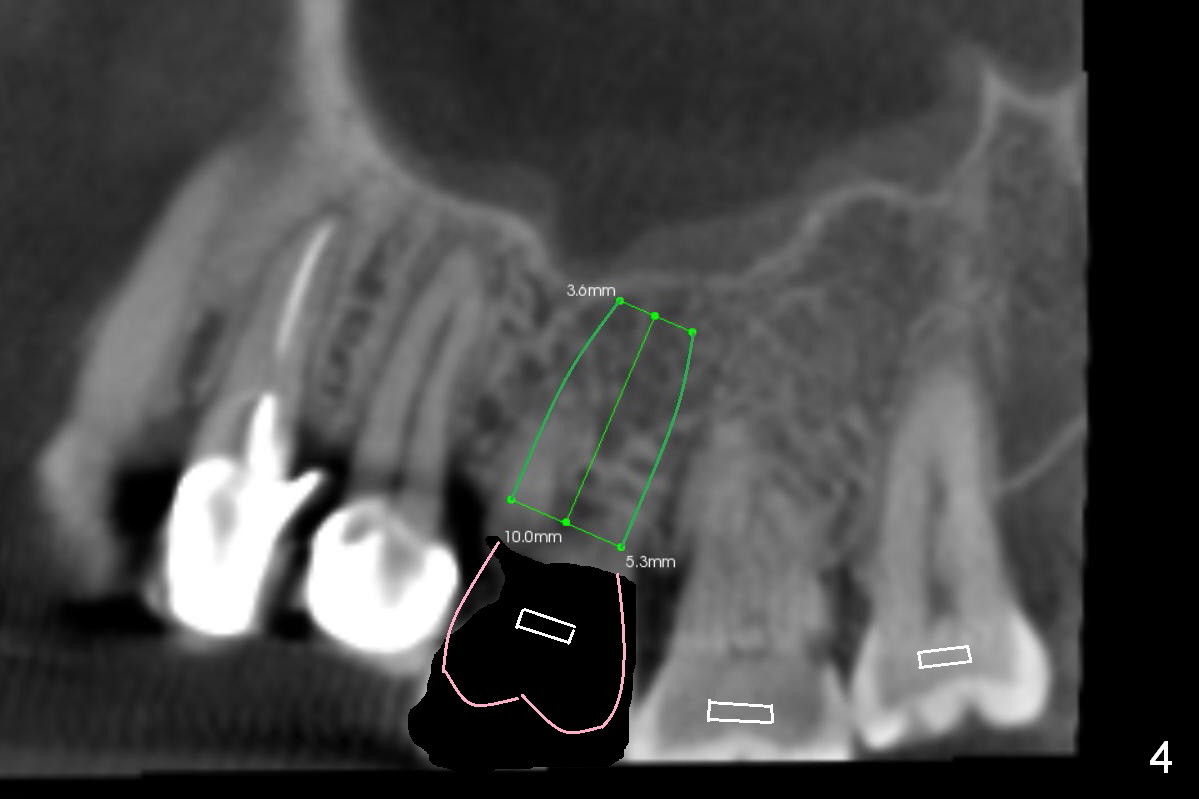

In addition to supraeruption of the teeth #2 and 3, the caries in the mesiobuccal root of #3 seems to be beyond salvation (Fig.1,2 arrowhead). When the implant at #3 is osteointegrated, a provisional restoration is placed (Fig.4 pink). Brackets (white boxes) are placed at differential levels among #1-3 to initiate regional orthodontic treatment using #3 as an anchorage. Mini-implants are placed if necessary. The tooth #1 is extracted after the limited ortho. Scaling & root planing will be done first.